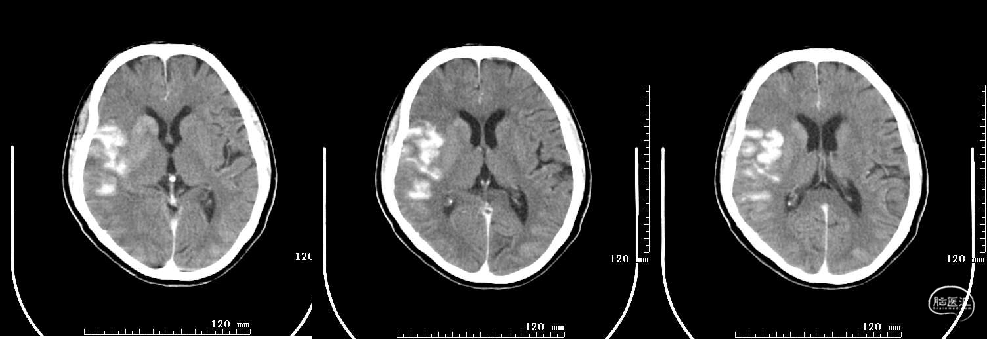

头颅CT:多发性腔隙性脑梗死,脑白质变性,右侧大脑中动脉高密度征?

头颅MRI+DWI+MRA:右侧额颞叶及侧脑室旁急性脑梗塞,右侧大脑中动脉闭塞?右侧颈内动脉破裂孔段狭窄?

术后即刻:

术后查体:神清,部分运动性失语,双眼无凝视,双侧额纹对称,鼻唇沟对称存在,伸舌居中,示齿口角右歪,左肢肌力IV+级,右肢肌力V级,肌张力适中,病理征未引出。

NIHSS评分2分(面瘫1分、语言1分)。